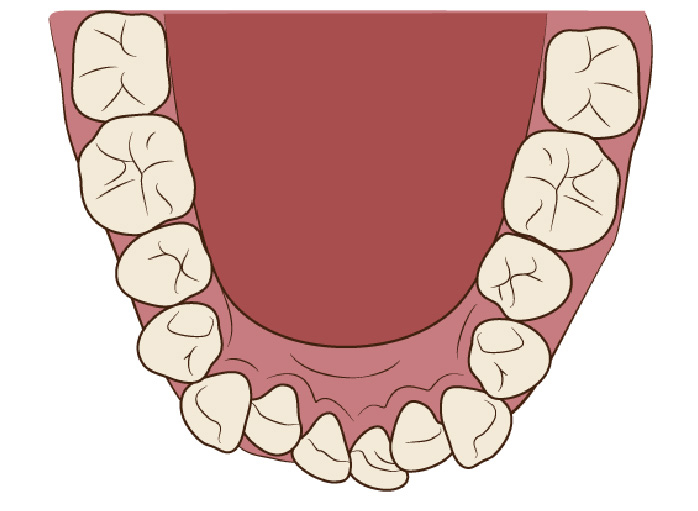

狭い歯列(狭窄歯列)によって、舌が歯列の中に収まらない状態です。

●高口蓋 ●低位舌 ●口呼吸

狭窄歯列(高口蓋)

狭窄歯列(低口蓋)

狭窄歯列(低位舌)

右のように、狭窄歯列だと舌は、狭い歯列に阻まれて、前方や上方の口蓋に自由に動くことができません。その結果、舌は低い位置(低位舌)にあり、前方に出ず後方に位置するので、気道が狭くなってしまっています。

一方、左のように、広い歯列だと舌は、前方にも上方にも自由に動けるので、舌は普段は口蓋についていて鼻呼吸が無理なくできているのです。

舌が正常な位置にある

舌が低い位置にある

舌の正しい位置

正しい位置

低い位置

狭い歯列(狭窄歯列(きょうさくしれつ))

高口蓋(上顎が深い→鼻腔が狭い)

舌が歯列に納まらない→低位舌

歯並びが悪い

かみ合わせが悪い